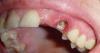

Андрей Опубликовано 21 сентября, 2009 Поделиться Опубликовано 21 сентября, 2009 Опорный зуб сгнил до такой степени, что его пора удалять, после чего можно поставить 2 имплантата и на них две коронки. Ссылка на комментарий

Андрей Опубликовано 21 сентября, 2009 Поделиться Опубликовано 21 сентября, 2009 Как быстро гниют зубы? Еще 5 мес. назад два разных врача утверждали, что он еще очень крепкий и простоит долго 2 имплантанта? Не часто? нельзя на одном это все расположить?Судя по фотке, клык уже сгнил глубоко под десну. Может его еще и можно спасти, но для этого придется либо вытягивать крень из под десны брекитами, либо делать хирургическое удлиннение. У Вас есть его рентгеновский снимок этого зуба? На одном имплантате здесь не получится. Основное правило - сколько зубов отсутствует, столько нужно имплантатов. Ссылка на комментарий